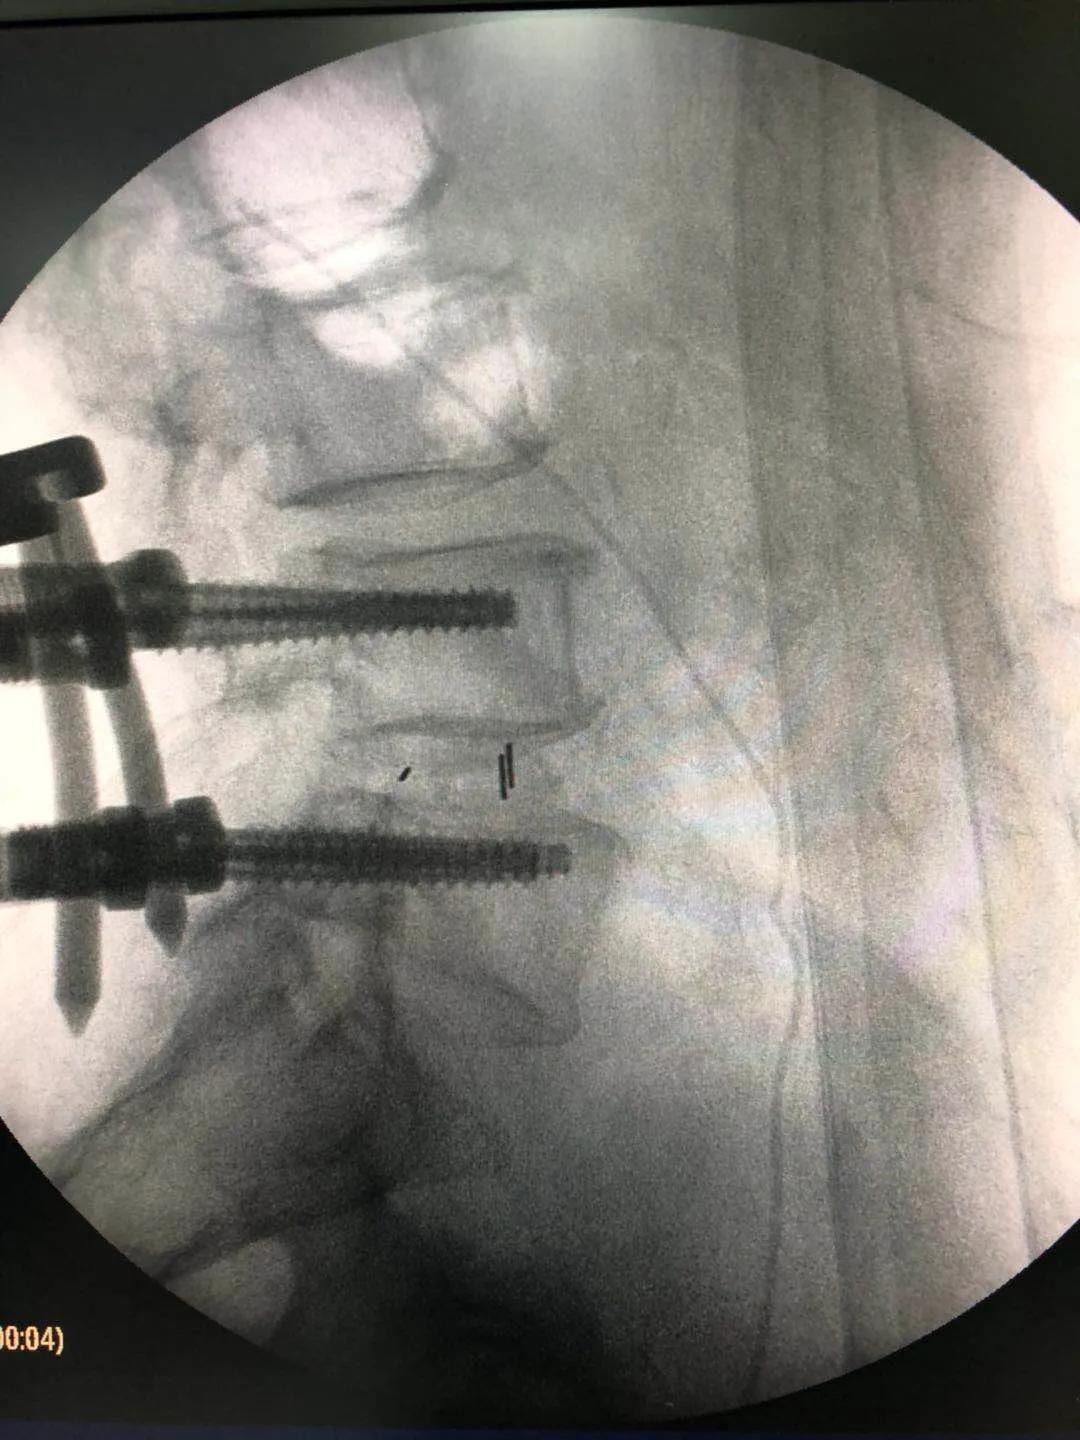

海安市中医院副院长、骨伤科主任魏爱淳主任中医师接诊后,为其制定了UBE(单侧双通道内镜微创技术)治疗方案。做好各项术前准备后,魏爱淳副院长、蒋剑锋主任和他们的手术团队在专家指导下,采用UBE专用综合器械包和专用等离子射频手术系统,成功为患者实施了UBE技术下L3/4椎管减压,L4/5椎管减压、椎间植骨融合术,手术只有5个微创小切口,术后江先生的双下肢疼痛、麻木症状缓解,手术达到预期的效果,获得了患者及家属的一致称赞。

海安市中医院骨伤科是南通市重点中医专科之一,配备的现代化设备有:进口全套椎间孔镜系统、椎间盘镜系统、微创扩大通道及进口C臂机多台,常规开展椎间孔镜手术、椎间盘镜手术、MIS-TLIF、经皮椎弓根、螺钉内固定手术、经皮椎体成形术、经皮椎体后凸成形术等多项脊柱微创手术治疗。